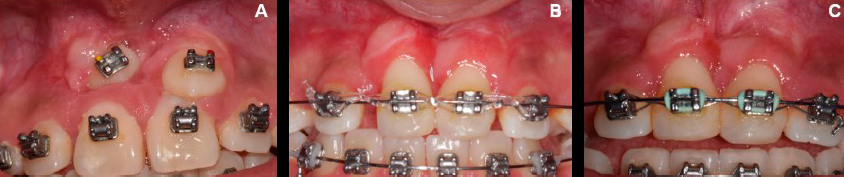

Diente 13: En los parámetros clínicos el IP=0, presentó ausencia de placa en el área gingival; IG=0, mostró encía con ausencia de inflamación, de hemorragia y alteración del cambio de color, la PB<4mm, con ausencia de bolsas periodontales (Tabla 1), TQ de 5mm (Figura 5. A-C).

Figura 5 Valoración de tejido queratinizado obtenido alrededor del diente 13, posterior a la cirugía. El tejido siguió al diente durante sus movimientos y es comparable con el de los dientes adyacentes. A. 6 meses posquirúrgicos. B. Al año posquirúrgico. C. A los dos años posquirúrgicos.

Dientes 13 y 23. En los parámetros clínicos el IP=0, presentó ausencia de placa en el área gingival, IG=0, mostró encía con ausencia de inflamación, de hemorragia y de cambio de color, PB<4mm, con ausencia de bolsas periodontales (Tabla 1), TQ de 5mm y 3mm para los dientes 13 y 23 respectivamente (Figura 8. A-C). La PEC mostró una puntuación de 6 para el nivel del margen gingival en los dos caninos, es decir, ausencia de recesión gingival; en cuanto al contorno del tejido marginal, el resultado fue de 1 para ambos dientes, evidenciando un contorno marginal festoneado; la variable de textura con puntuación de 0, mostró la presencia de una cicatriz alrededor de los dos caninos; para el color, la puntuación fue de 0 para el diente 13, mostrando una variación del color en relación a los dientes adyacentes y, de 1 para el diente 23, evidenciando una adecuada integración con los tejidos blandos adyacentes; por su parte, la LMG se mostró alineada con los dientes adyacentes, obteniendo una puntuación de 1 en los dos dientes. En total se obtuvo puntuación de 8 para el diente 13, y de 9 para el diente 23 (Tabla 2).

Figura 8 Valoración de tejido queratinizado obtenido alrededor de los dientes 13 y 23, posteriores de la cirugía. El tejido siguió al diente durante sus movimientos y es comparable al de los dientes adyacentes. A. 6 meses posquirúrgicos. B. Al año posquirúrgico. C. A los dos años posquirúrgicos.